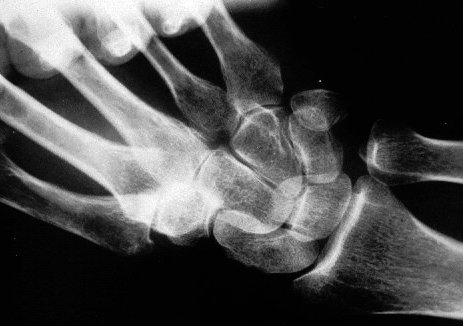

Kinematic wrist clenched fist ulnar deviation Xray view

Xray Beam angle: 90 degrees.

This view puts the scaphoid more on profile, and stresses the scapholunate ligament.